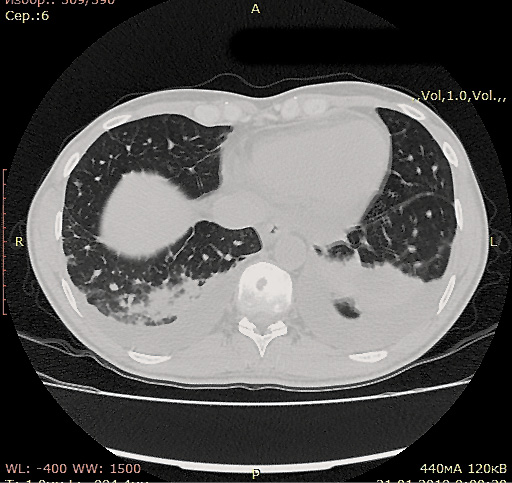

В связи с высоким риском рецидива после выполнения ВДХТ с аутоТГСК планировалось продолжить консолидирующую терапию Bv в монорежиме до 16 введений. В декабре 2018 г. проведено первое введение Bv. Накануне следующего введения отмечен подъем температуры до 38,5°С без озноба и катаральных явлений. На КТ органов грудной клетки выявлены очагово-инфильтративные изменения в средней и нижней долях обоих легких, двусторонний гидроторакс (рис. 4).

Рис. 4. КТ органов грудной клетки (очагово-инфильтративные изменения в средней и нижней долях обоих легких, жидкость в плевральных полостях).